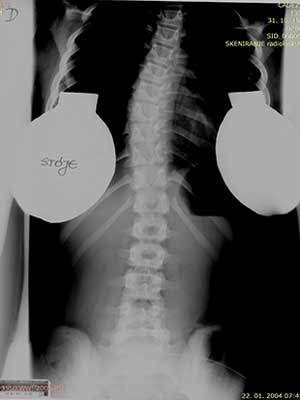

Pojdimo nazaj v leto 2004. 20 let nazaj, ko so mi, kot večini na sistematskem pregledu ugotovili začetek skolioze. Sledil je obisk pri ortopedu, slikanje in potrditev diagnoze začetka skolioze.

V tistem trenutku ni bila ta diagnoza nič posebenga, skolioza je bila še v začetku saj je merila 28°v prsnem delu in 15° ledvenem delu (Ko danes berem te stopinje… skolioza je že konkretno napredovala in pametno bi bilo takoj predpisati vaje in steznik). Takrat so nam naročili, naj se vrnemo čez pol leta. Da bodo opazovali.

Moja hrbtenica leta 2004

Nismo ji/mi posvečali prevelike pozornosti, ker tudi ortopedi niso pokazali skrbi. In tako je minilo pol leta, ko sem zopet slikala svojo hrbtenico.

Skoliza se je poslabšala na 38° v prsnem delu in na 19°v ledvenem. Rahla panika, da če bo šlo na slabše bo potrebna operacija…